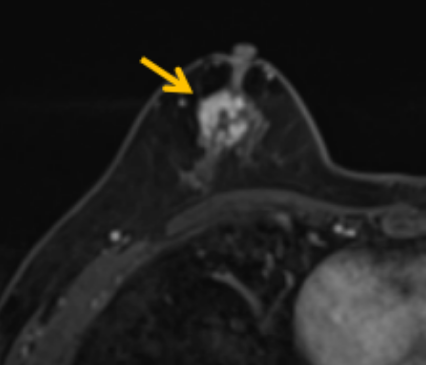

陳寶瑩評(píng)估圖像后發(fā)現(xiàn)病變?yōu)閮H僅在磁共振增強(qiáng)時(shí)顯示,為非腫塊樣病變,比較散,必須取得足夠多的組織才能確保病理檢查的準(zhǔn)確性,常用的核芯針活檢獲取的組織較少,因此最終確定了磁共振引導(dǎo)下行真空輔助抽吸旋切活檢。取得患者及家屬認(rèn)可后,陳寶瑩帶領(lǐng)團(tuán)隊(duì)開(kāi)始進(jìn)行術(shù)前準(zhǔn)備。

針對(duì)患者乳房小固定難度大這一問(wèn)題,陳寶瑩通過(guò)巧妙體位和固定器的調(diào)整,順利固定好乳房。經(jīng)過(guò)磁共振多模態(tài)掃描,陳寶瑩找出病變活性成分相對(duì)集中區(qū)域,精準(zhǔn)確定穿刺路徑,置入引導(dǎo)針、旋切針,到位后多角度旋切取出足量組織,拔除旋切針后即時(shí)行磁共振掃描,精準(zhǔn)取得組織且術(shù)區(qū)出血很少,遂加壓包扎,整個(gè)過(guò)程非常順利,旋切活檢后患者回家休息。兩天后隨訪,李女士沒(méi)有任何不適,五天后皮膚上幾毫米的小切口已經(jīng)愈合。最終病理結(jié)果證實(shí)為乳腺導(dǎo)管原位癌,為早期乳腺癌,為患者后續(xù)針對(duì)性治療奠定了基礎(chǔ)。